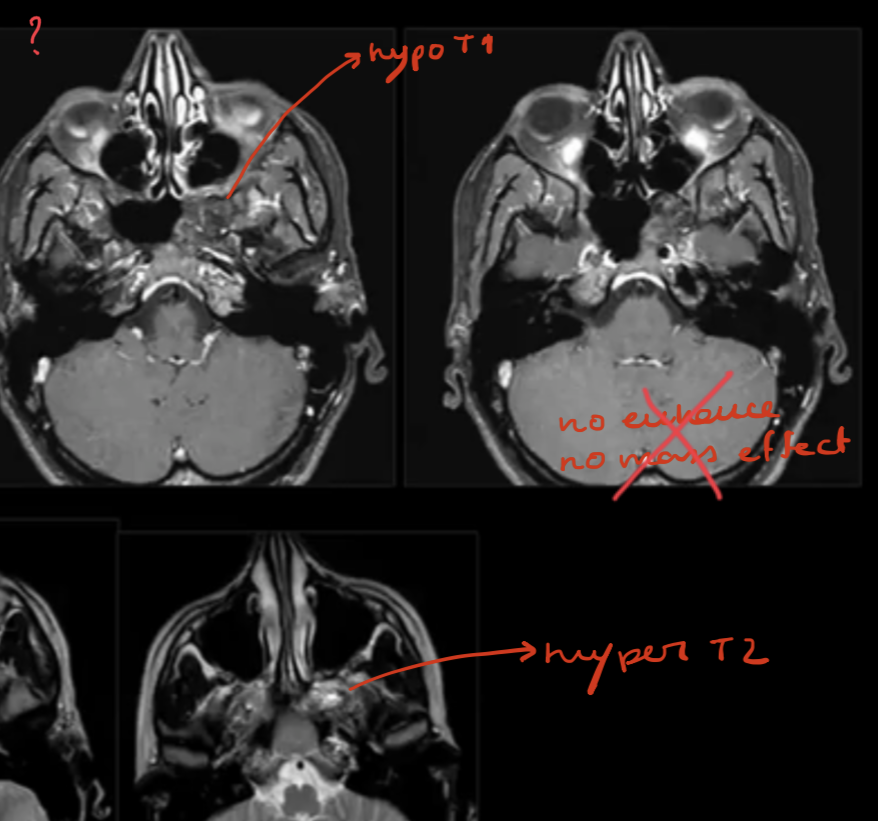

Arrested pneumatization in CT/MRI?

?

Arrested Pneumatisation

DDx of Arrested Pneumatization?